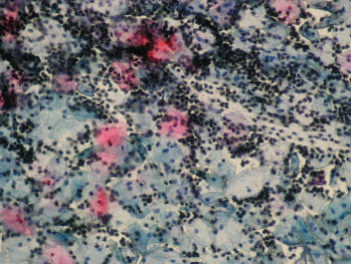

8. Препарат рідинної цитології це:

| • |

|